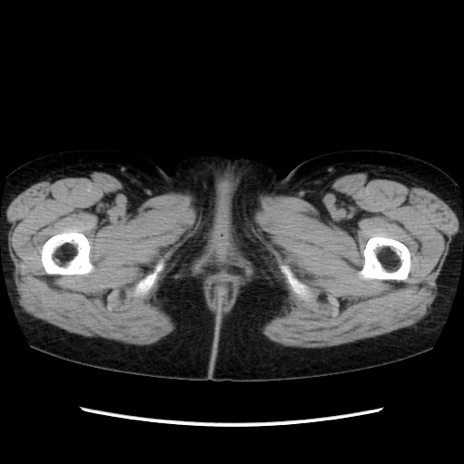

症例32(横断像)

【症例】40歳代 女性

【主訴】上腹部痛、嘔気・嘔吐

【現病歴】約9時間前頃から急に上腹部痛、嘔気、嘔吐が出現。改善しないため救急要請。

【既往歴】子宮頚癌(広汎子宮全摘術、放射線療法)、腸閉塞

【身体所見】腹部:平坦、軟、腸雑音亢進、上腹部を中心に腹部全体に圧痛あり。

【データ】WBC 8400、CRP 0.03